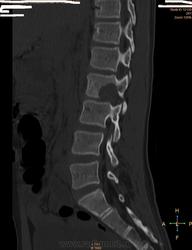

Здравствуйте коллеги.Прошу ваши помощи больной 1998 г.р. беспокоять боль поясничной области справа.Болеет в теч месяца, связывает с резким движением.Лечились по поводу почки без эфекта. Анализ не здали.Травму исключает. МРТ от 21 .10.2013 г. МР признаки участка патологич. измен. сигнальных характеристок с перифокальным трабекулярным отеком в теле и правой дужке позвон L2.Паравертабр. мягкотканный компонент в правой корешковой воронки на уровне L2-3.Этиология?Не исключается наличие осложненной переломы гемангиомы тела L2.Дифференцировать специфическим спондилитом .Анатомически суженный спинно- мозговой канал. Со слов матери костные фтизиатры исключили свое.Ваше мнение.